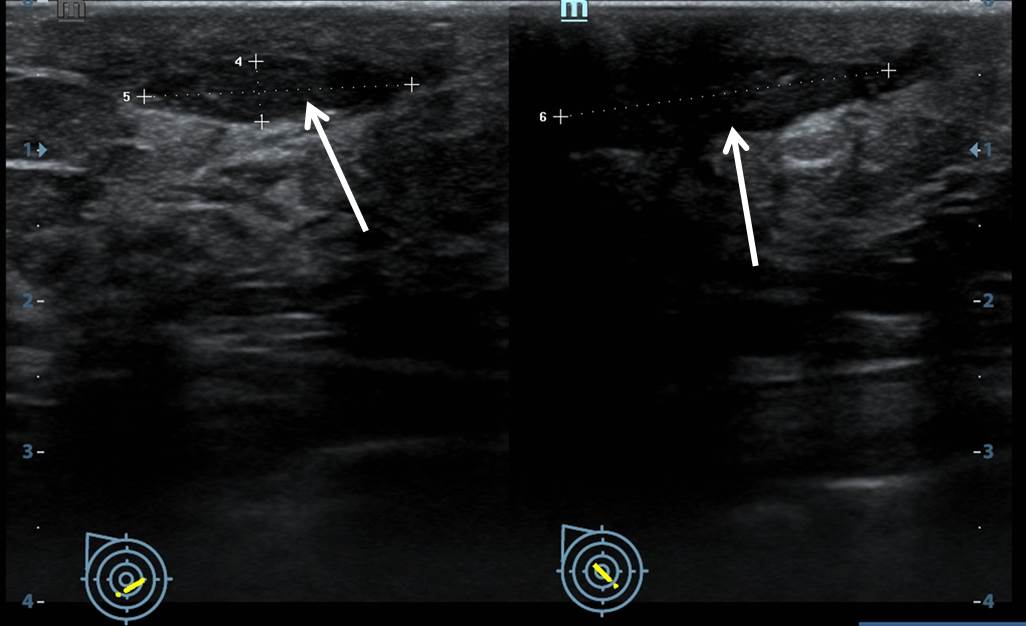

Mastitis Ultrasound. Blocked milk ducts and mastitis can be treated with therapeutic ultrasound, along with lymphatic drainage and Kinesiotaping Therapeutic ultrasound has been reported to alleviate inflammation and edema when supervised by a trained professional